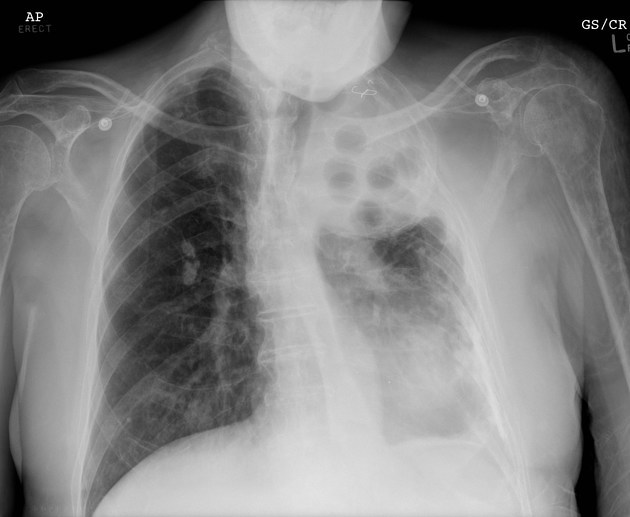

CLINICAL HISTORY:

32yo Female

Dyspnoea

FINDINGS:

Bilateral reticulonodular shadowing with diffuse cystic changes.

Lung volumes are preserved.

No pleural abnormalities demonstrated.

Heart size is normal.

Hila and mediastinal contours are normal.

IMPRESSION:

Lymphangioleiomyomatosis

DIFFERENTIAL DIAGNOSIS:

Langerhans Cell Histiocytosis (Usually has a smoking history and present in an older age group)

Overlapping emphysematous and granulomatous disease